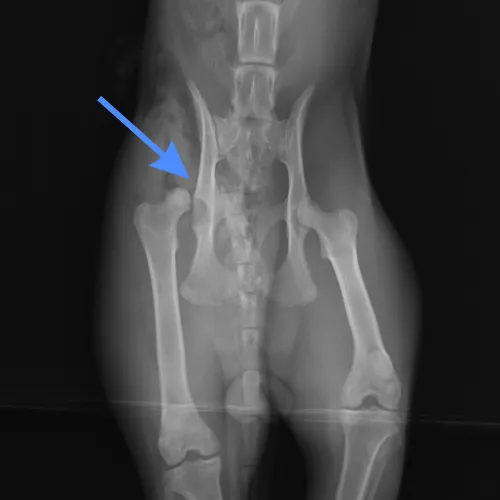

Tanı

Travma olasılığı nedeniyle tam bir genel muayene ve ortopedik değerlendirme yapılmalıdır. Kalçanın çıkmasına sebep olan darbe ya da travma, idrar sistemine, akciğerlere, kalbe veya diğer vücut organlarına da zarar verebilir. Hastanın anesteziyi etkileyebilecek diğer yaralanmalar veya organ rahatsızlıkları açısından değerlendirilmesi için ek tanılar gereklidir. Organ fonksiyonunu tam olarak değerlendirmek, hasarın boyutunu belirlemek, önceden var olan tıbbi sorunları belirlemek ve anestezi planlaması için ek kan çalışmaları endikedir. Bu tetkik ve muayenelerin ardından fiziksel muayeneyi radyografik muayene takip eder ki bazen bunun için hastanın sakinleştirilmesi ya da anesteziye alınması gerekebilir. Kalçaların radyografileri çıkığın yönünü ve eklem yüzeylerinin kırılması gibi eklemdeki diğer ilişkili hasarları değerlendirmek için yapılır.